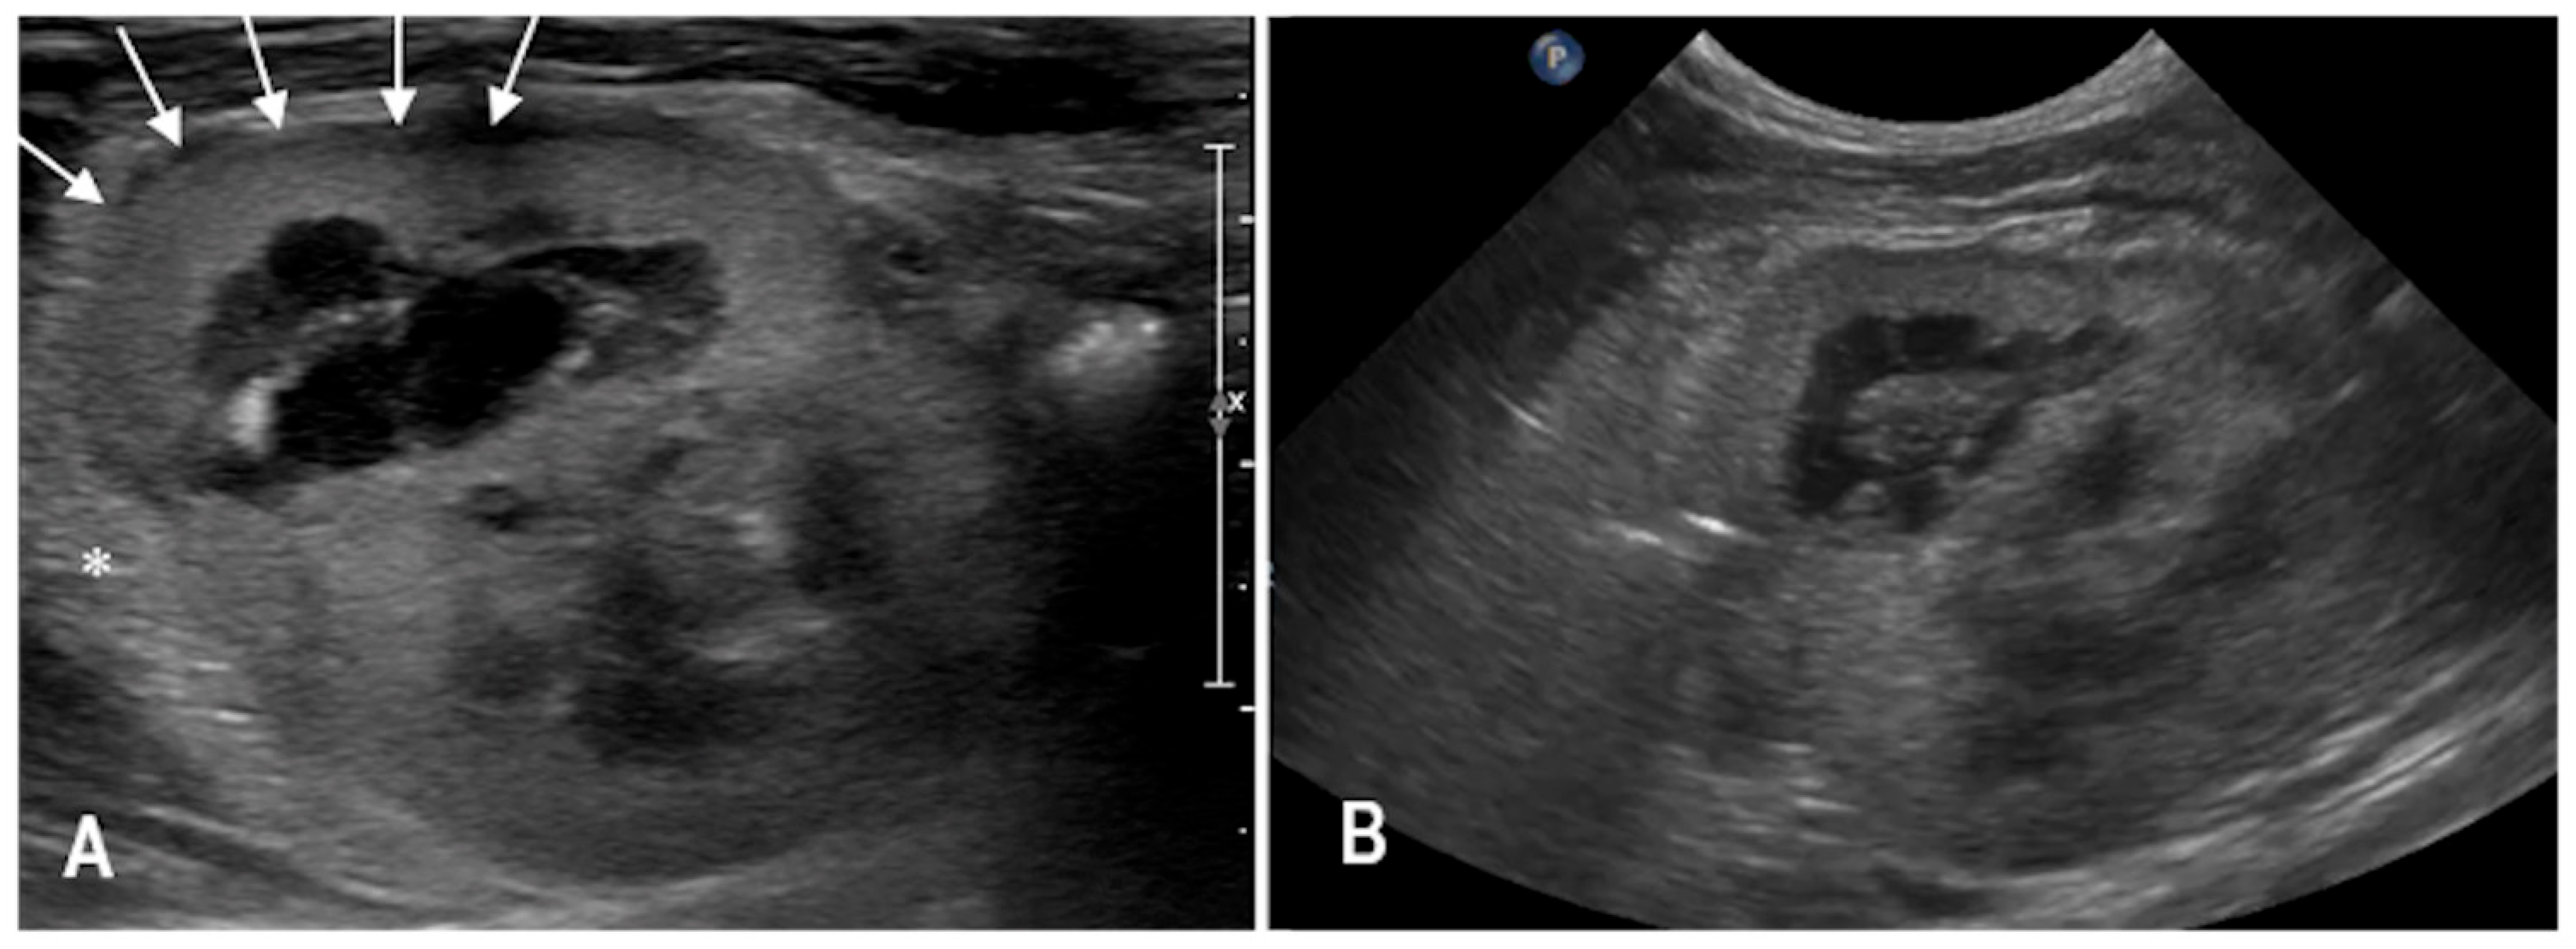

3.3. Case 3